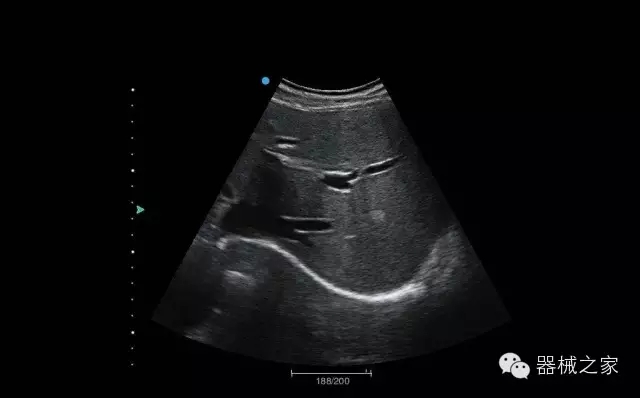

臨床圖片賞析

結(jié)甲